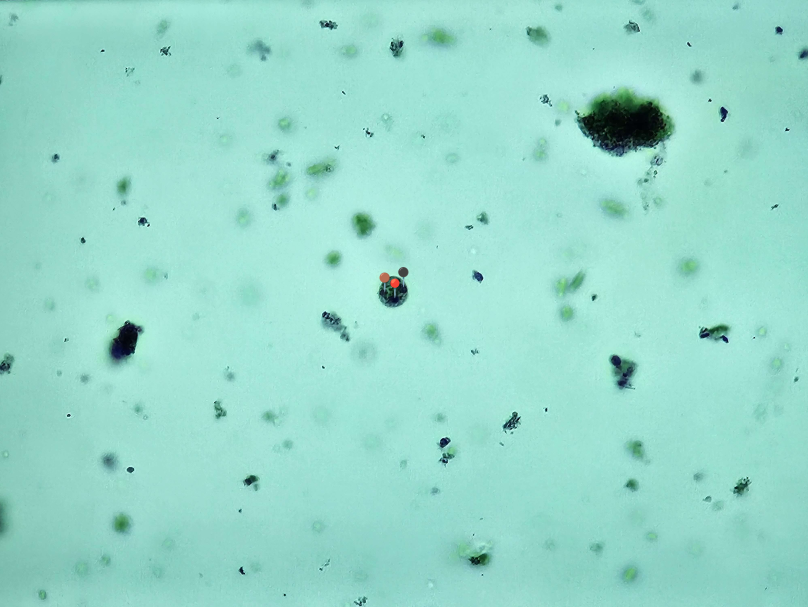

🩸🦠 Plasmodium sp.

🔵🟣 - schizont segmenter;

🔴️ - stadium pierścienia.

😷❓ Parazytoza: Malaria